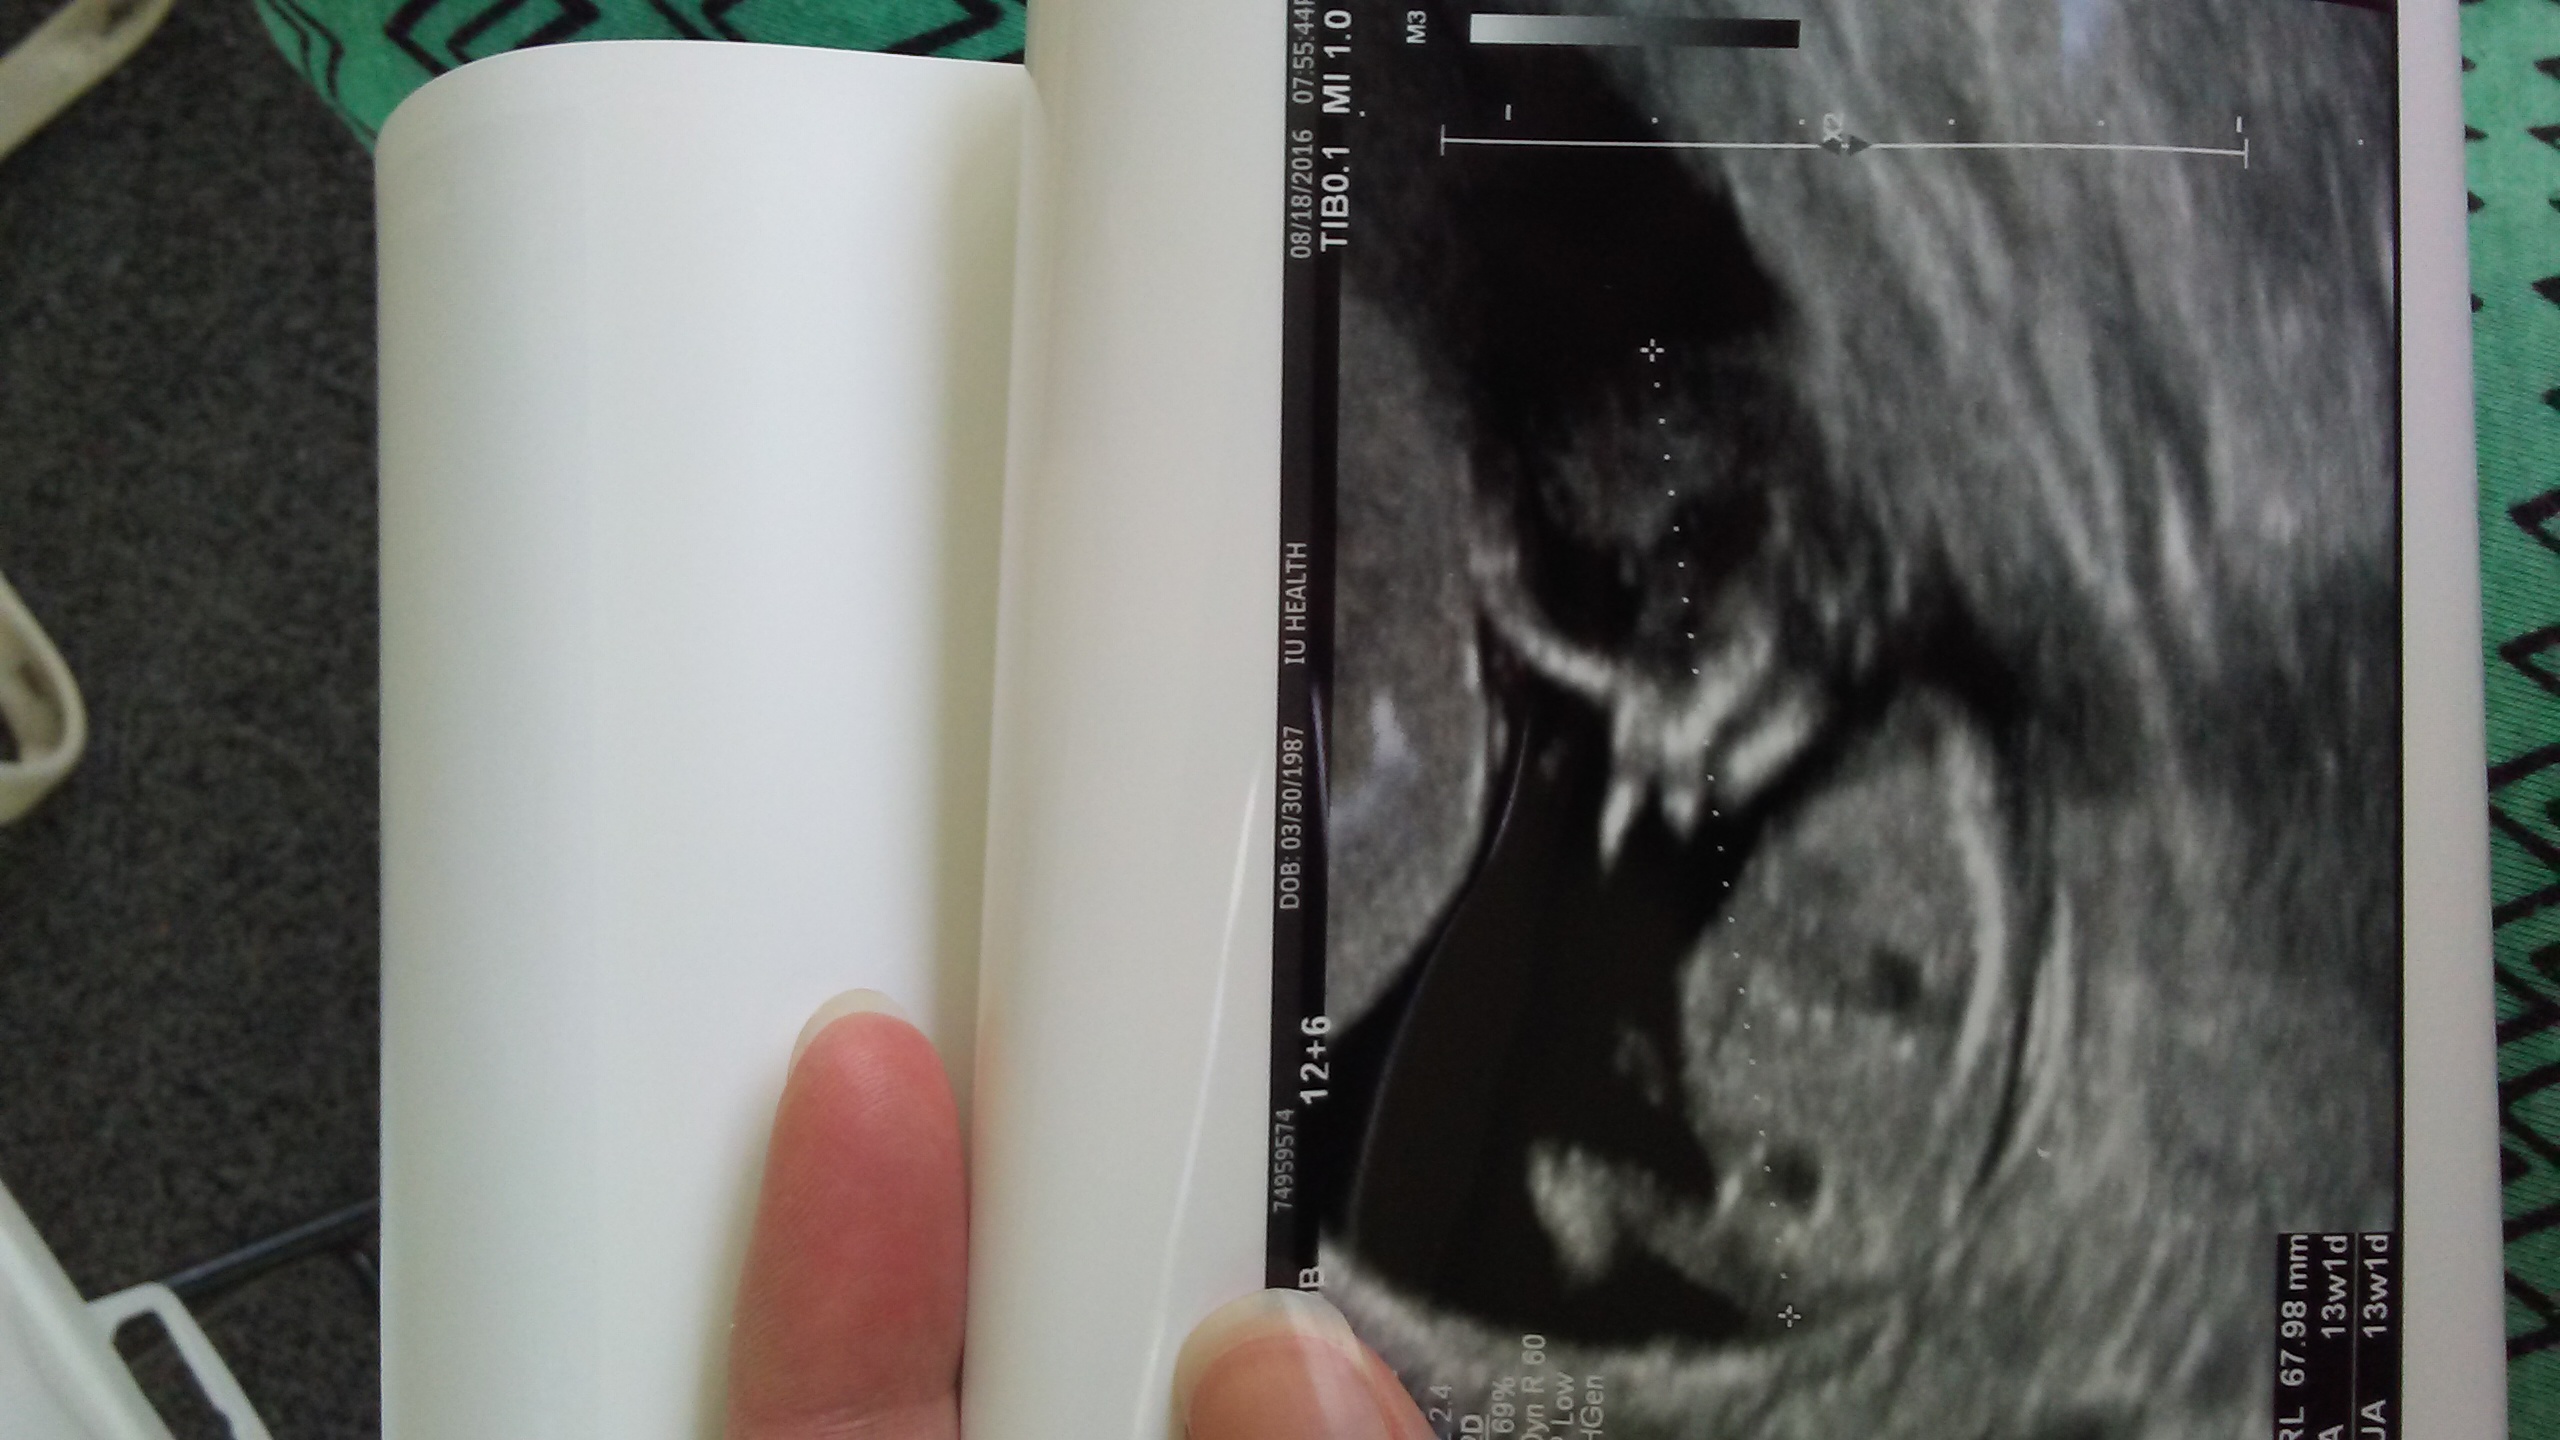

Baby is measuring 13 weeks 2 days... Attachment 32852 Attachment 32853Attachment 32854